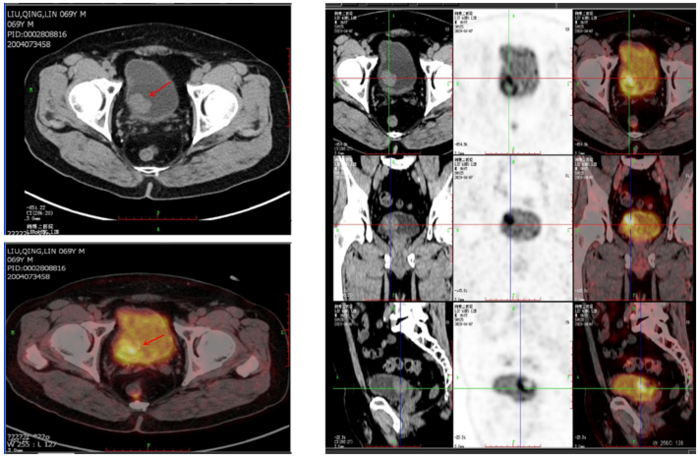

检查后核磁共振显示: 膀胱右后壁可见不规则肿物,约30*20mm大小,浸润肌层可能性大,盆腔未见肿大淋巴结。全身PET-CT显示:1.膀胱肿瘤电切术后改变,膀胱内不规则糖代谢显著增高的高密度影,考虑肿瘤残留。

叶定伟教授膀胱癌多学科团队经过充分的评估和讨论之后,确定王先生的临床诊断是膀胱高级别肌层浸润性尿路上皮癌、肿瘤分期:cT2N0M0。团队制定了个体化的治疗方案,建议王先生首先做最大化的经尿道膀胱肿瘤电切术,将膀胱内的病灶完全切除。手术后王先生开始接受吉西他滨加顺铂化疗联合放疗的治疗方案